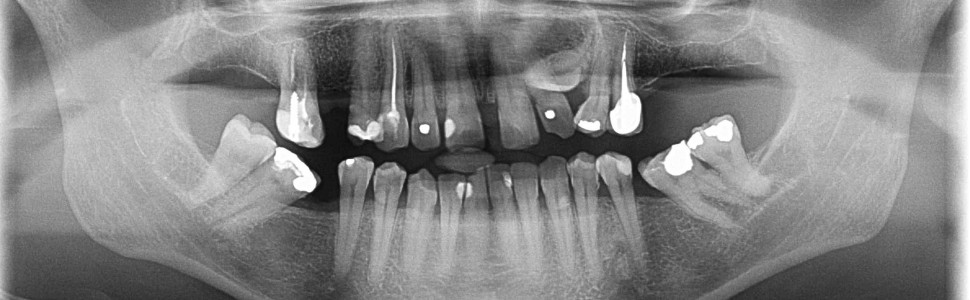

Opis przypadku. U 55-letniej pacjentki na podstawie badania tomografii stożkowej stwierdzono zatrzymany ząb 23 o nieprawidłowym kształcie i położeniu w poprzek łuku na szczycie wyrostka zębodołowego, co uniemożliwiało sprowadzenie go do jamy ustnej. W związku z tym zaplanowano jego usunięcie z jednoczesną augmentacją wyrostka zębodołowego allogennym blokiem kostnym z następczym leczeniem ortodontycznym, w celu odtworzenia luki pod implant w miejscu 23.

Zakwalifikowany do ekstrakcji zatrzymany ząb 23 został usunięty; jednocześnie wykonano augmentację kości wyrostka zębodołowego przy użyciu allogennego sterylizowanego radiacyjnie bloku kostnego. Po upływie pół roku rozpoczęto leczenie ortodontyczne, którego efektem było uzyskanie luki pod zaplanowany wcześniej wszczep kostny.

Po półtorarocznym leczeniu ortodontycznym osadzono koronę protetyczną na wszczepie wprowadzonym w ortodontycznie przygotowaną lukę w miejscu zęba 23.